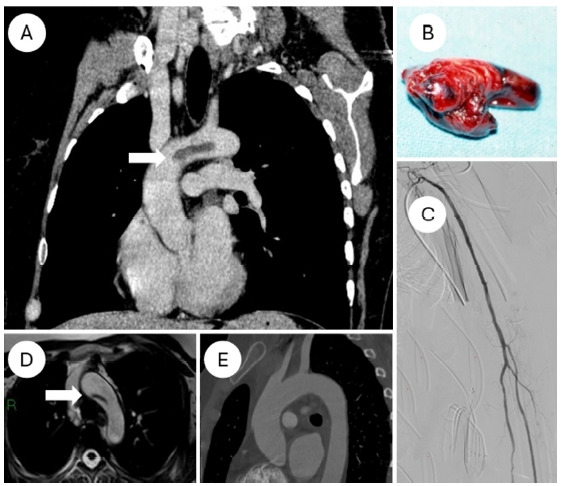

Floating thrombus involving the aortic arch in a woman.

一名女性主动脉弓上的漂浮血栓。